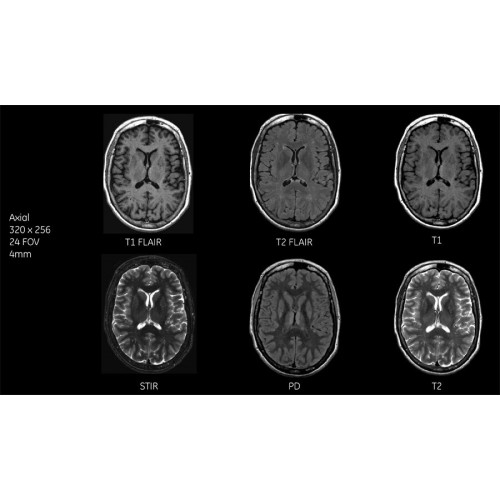

Система SIGNA Pioneer воплощает поразительные достижения в области визуализации. Передовая технология Total Digital Imaging (TDI) позволяет добиться большей четкости изображений и на четверть повысить соотношение сигнал/шум.

• Технология Direct Digital Interface (DDI) использует независимый аналого-цифровой преобразователь для оцифровки сигнала от каждого из 97 радиочастотных каналов, что обеспечивает значительное увеличение качества за счет уменьшения фонового шума.

Благодаря революционному программному пакету Silent Suite уровень шума снижается до 77 дБ, что всего на 3 дБ выше уровня окружающей среды. Программный пакет Silent Suite теперь включает полный пакет приложений для исследования ЦНС (T1, T2 FLAIR, DWI10, МРА). Кроме того, мы расширили возможности визуализации Silent за пределы ЦНС для исследований скелетно-мышечной системы и позвоночника. Silent Suite – платформа, содержащая в себе все импульсные последовательности для бесшумного сканирования.